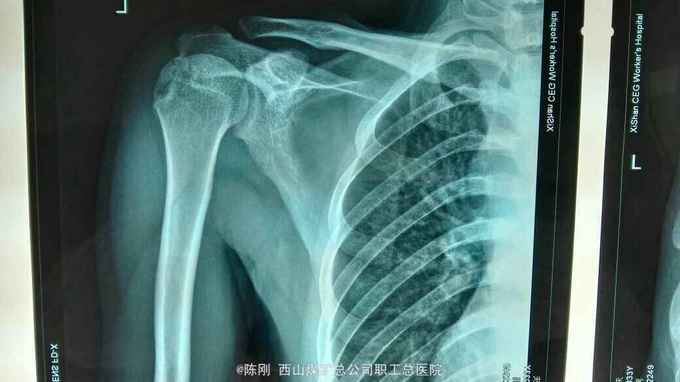

复查x线片

左外踝毁损伤,左肱骨脱位半大结节骨折,左内踝骨折,右内,后踝骨折